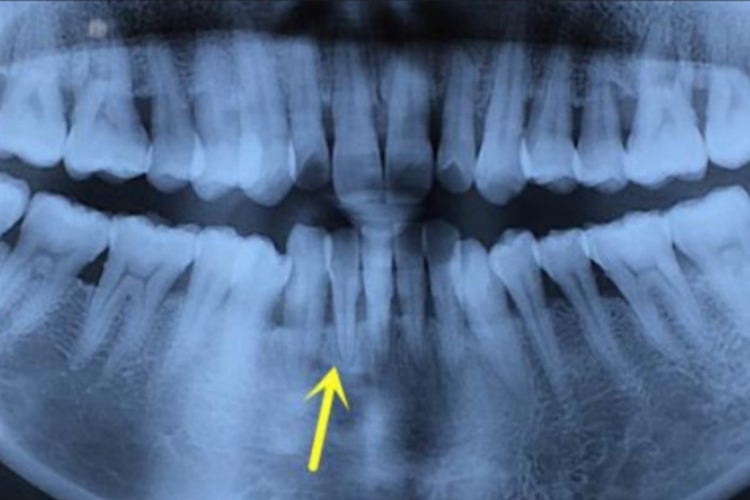

牙槽骨位于人体口腔中,是上下颌骨包围和支持牙根的部分,颌骨上与牙齿相连接的骨性突起部分。由固有牙槽骨和支持骨组成,牙根支撑,呈凹槽状。X线片可见一条阻射线沿着牙周膜间隙相对应的透射线。